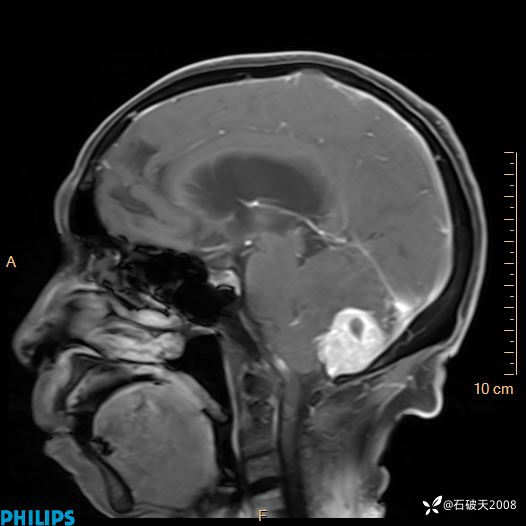

书上说这个肿瘤发生在幕下仅4.09%,你会想到它吗?(病理已公布)

女 86岁 主 诉:乏力1月

现病史:患者1月前活动出现双下肢乏力,无头晕、头痛、恶心、呕吐、肢体活动不利,休息后缓解,间断断发作,症状进行性加重,在家口服药物治疗(具体不详),效差,为进一步诊治,来我院,门诊按“乏力”收住我科,患者自发病以来,神志清,精神稍差,饮食睡眠欠佳,大小便正常,体重未见明显改变。

T1

增强矢状位